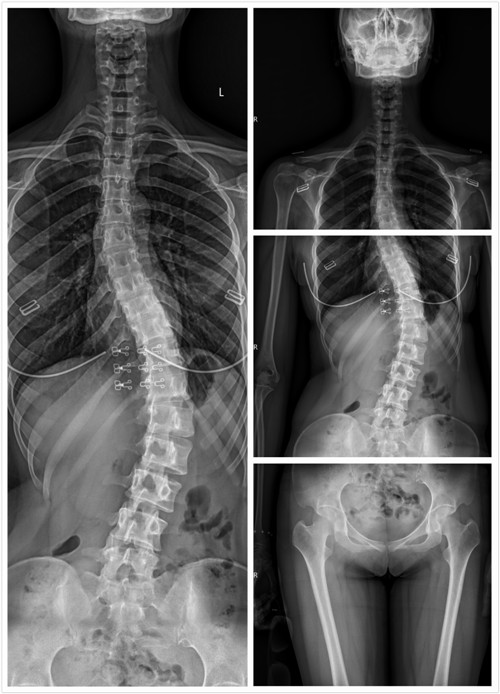

在一张照片上能观察到全脊柱一直是放射科医师及临床医师所希望的。全脊柱X线片对于脊柱侧弯的诊断、手术方案的制定、Cobb角度的测量等,都有着重要的参考价值。日前,交大二附院医学影像科购入的西班牙赛德科NOVA FA-C全自动悬吊摄影系统(DR拍片机),已顺利装机、调试和培训,该机器可一键定位(发射器与接收器一键跟随)、双板拍片(立位片与卧位片可在一个检查室进行)、自带床旁(直接在仪器旁对无法挪床的患者进行床旁射片)、图像拼接(将多张射片图像重叠合并生成全景或高分辨率图像)等新技术。

3月8日,在骨科与康复医学科的支持下,科室所有工作人员进行了图像拼接技术的培训及学习,顺利完成三例全脊柱和一例下肢全长的拼接摄影,取得了满意的效果。